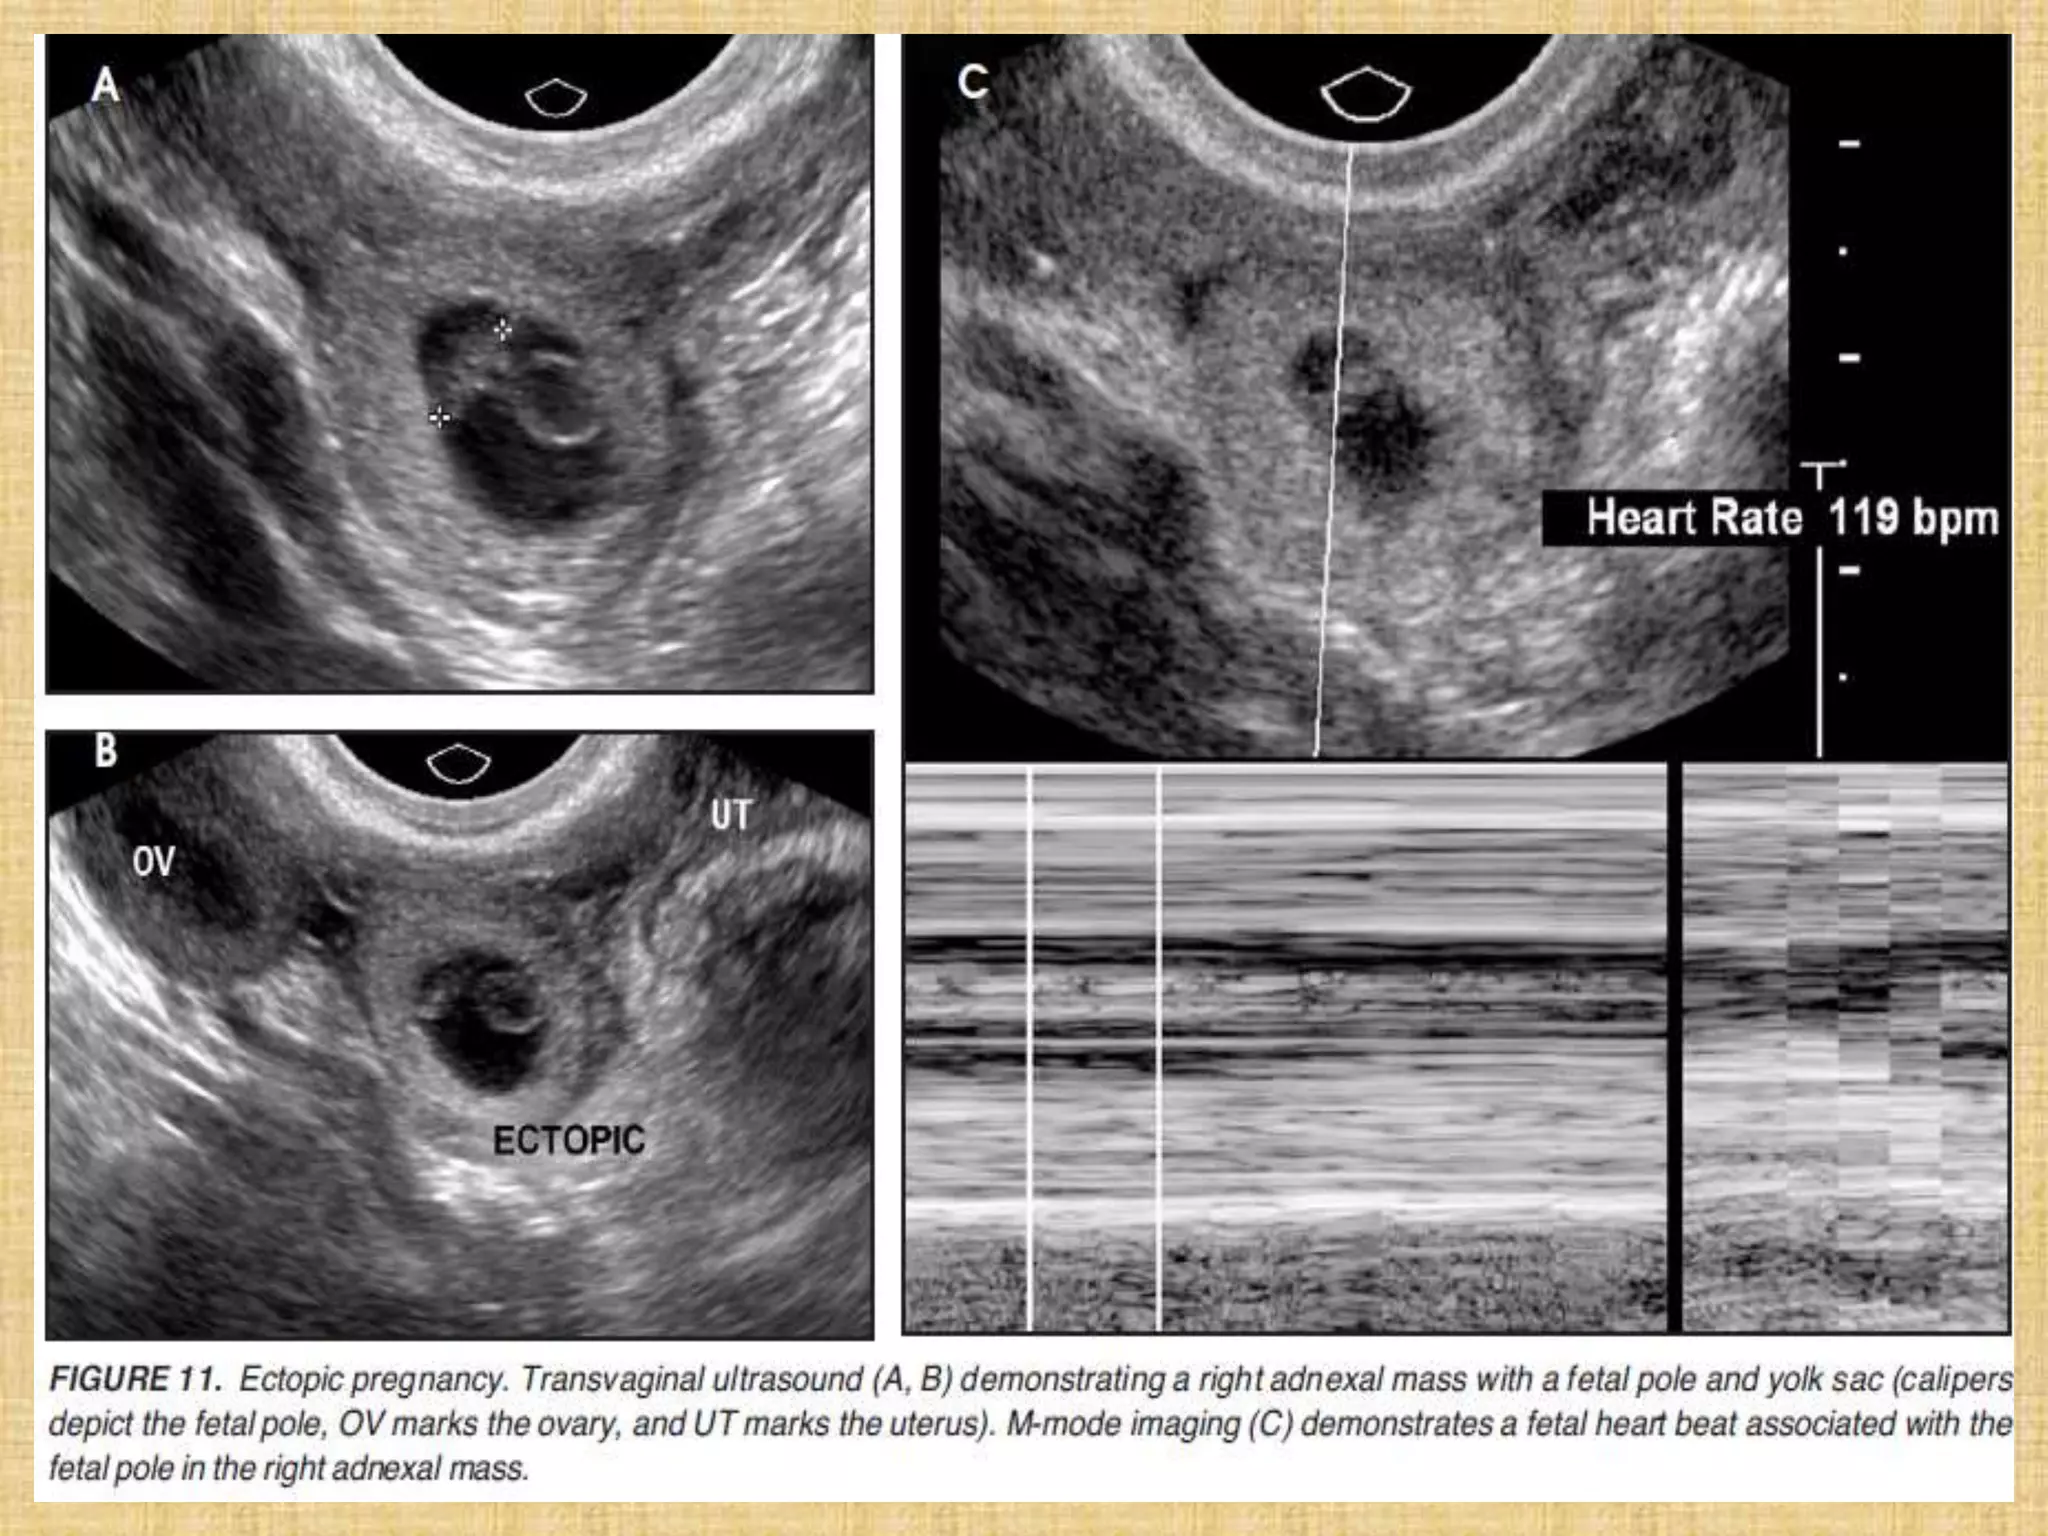

Ectopic pregnancy. Abdominal/pelvic CT. Image compatible with gestational sac in

the left adnexal region (arrow on A), separated from the uterine image (stars on A

and B) and from the ipsilateral ovary identified by visualization of the corpus

luteum (hollow arrow on B). Also, note the presence moderate amount of fluid in

the peritoneal cavity with foci of high density characterizing hematic content (L).

(A,B: contrast-enhanced axial sections in the portal phase).